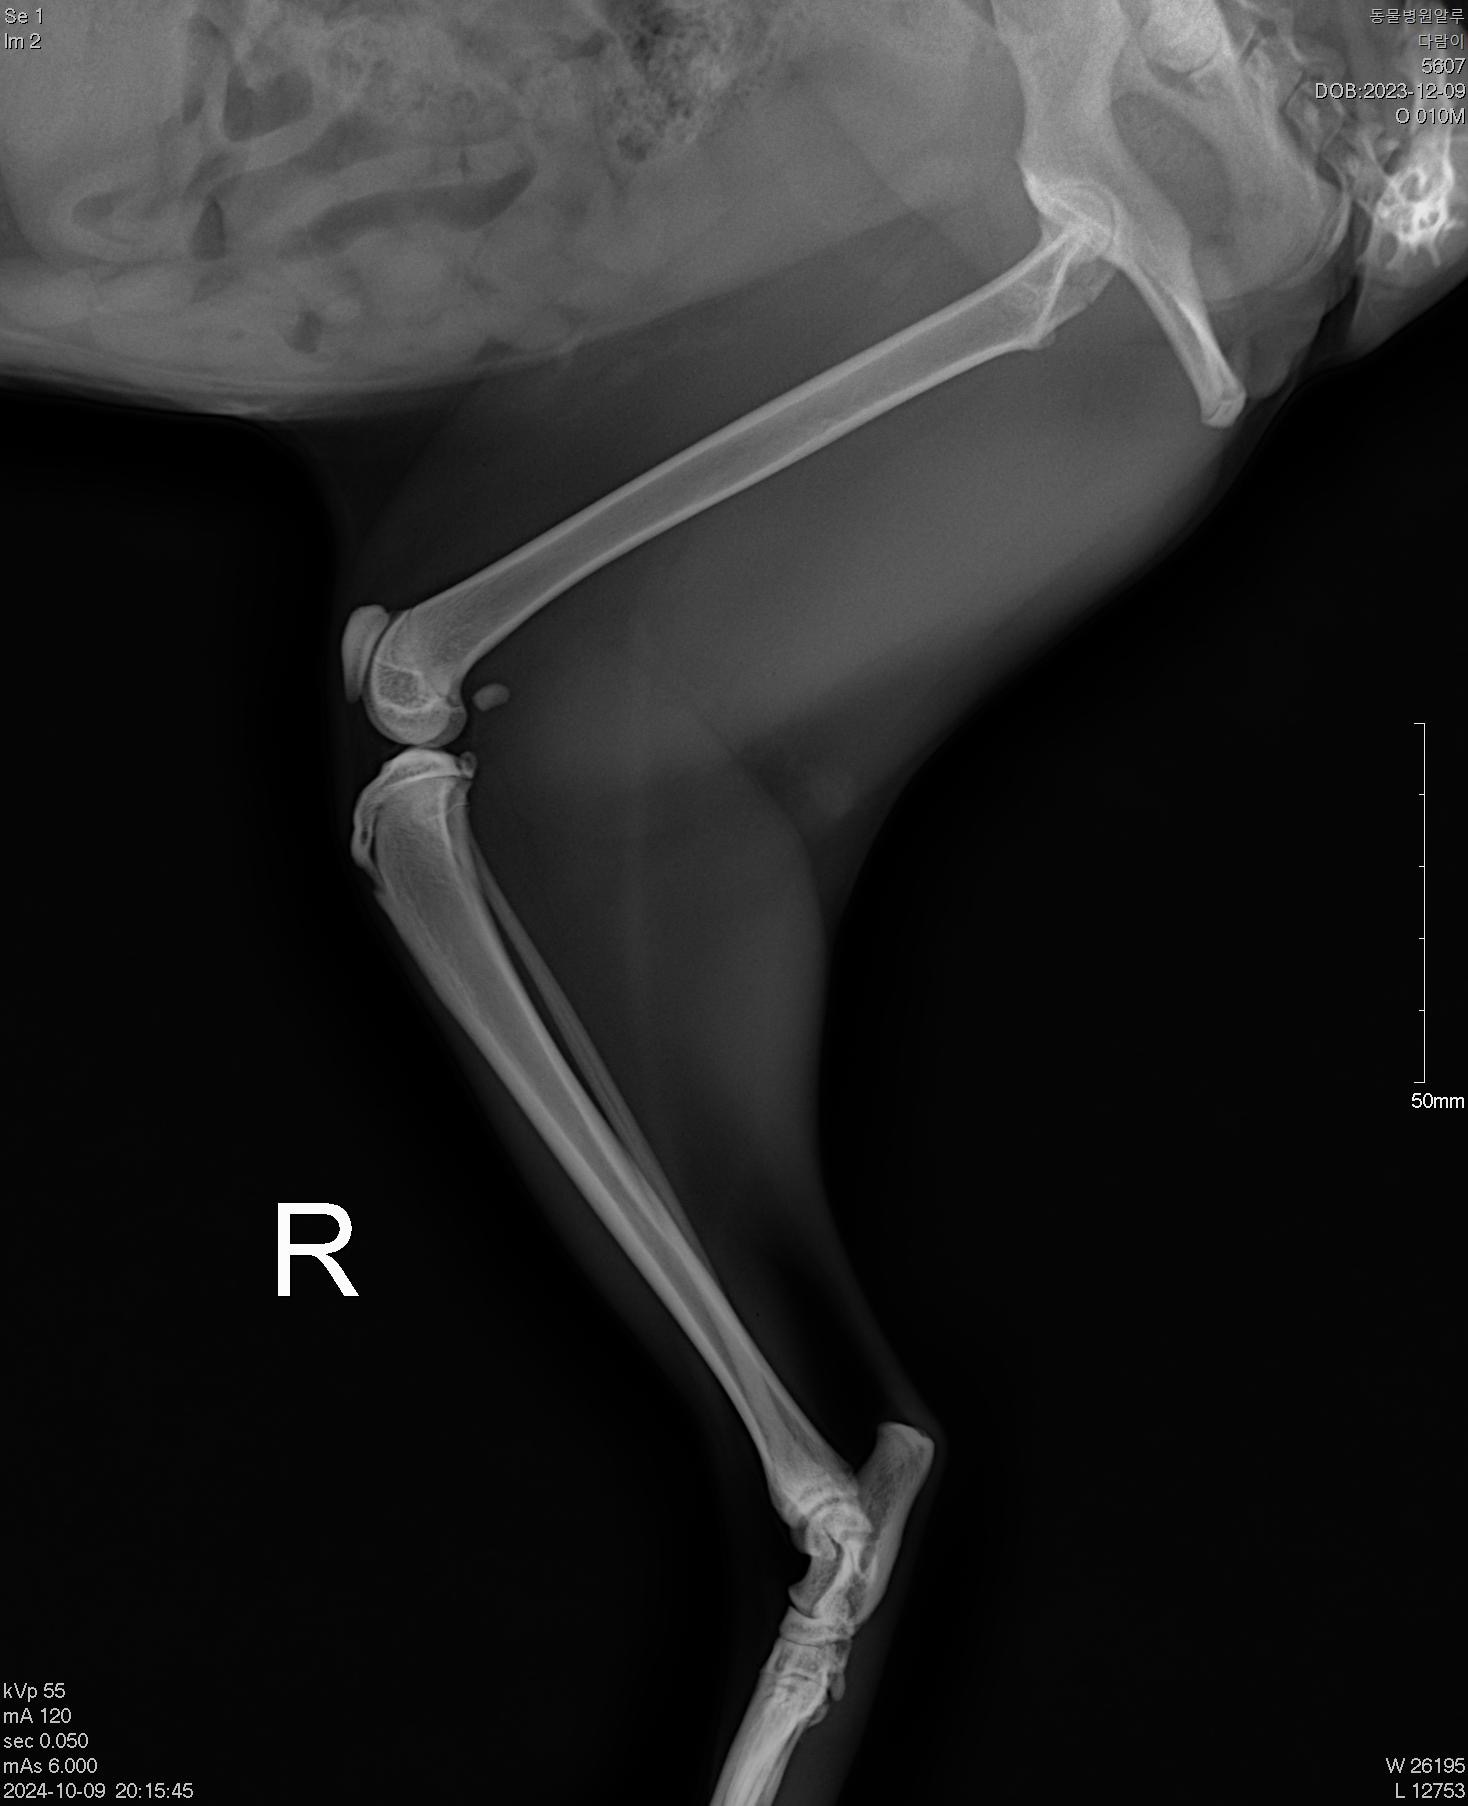

| 대상묘신청당시상태 | 암컷이고 아직 1년이 안된 10개월 정도로 추정됩니다. 다람쥐털 색을 닮아 다람이라고 이름 지었습니다. 6월에는 구청을 통해 TNR을 진행했는데 이후에도 저를 잘 따르고 매일 밥을 먹으러 오던 아이인데 이틀이나 안와서 걱정했는데 3일째 다리를 심하게 절뚝이면서 나타났습니다. 구조해서 치료하는 게 엄두가 안 나서 일단 밥과 항생제, 진통완화제(신경안정제)를 먹였습니다. 경과를 지켜보는 와중에, 다리를 다쳐서 이동이 불편한 건지 잠자리가 변변치 않은지 최근 아침저녁 기온이 떨어지자 감기까지 걸리고 말았습니다. 전처럼 밥도 잘 먹지 못하고 왼쪽 뒷다리를 다쳐서 그 다리는 땅에 디디지조차 못하는데 그 다리를 하고서도 밥자리로 나오는 모습이 너무 안쓰러워서 병원에 데리고 가서 일단 엑스레이라도 찍어봤습니다. 결국 골절이라는 진단을 받았고 수술이 불가피한 상태였습니다. 엑스레이 촬영 후 길에 둘 수가 없어 임시보호하며 치료지원 신청을 하게 되었습니다. |

골절 수술은 최대한 빨리 진행하는 것이 결과가 좋다고 해서 2차병원에 예약하자마자 바로 수술을 진행하고 4일간 입원하였습니다. 골절 구조의 어려움 때문에 발견 후 3-4일 정도 망설였는데 병원에서 골절은 골든 타임이 중요하다고 하셔서 다람이한테 미안해지는 순간이었습니다. 발견하자마자 수술을 했더라면 훨씬 뼈도 빨리 붙고 덜 아팠을 텐데. 다리 털을 밀고 보니 멍이 들어 있었습니다.(사진 참고)

골절 치료는 치료비 자체도 부담되고 치료 후의 과정이 쉽지 않아 고민이 많이 되었습니다. 수술 과정을 겪으면서 느낀 점은 골절은 골든 타임이 매우 중요한다는 것이었습니다. 발견 즉시 치료를 하는 것이 수술을 최소화로 할 수 있는 방법이라는 것을 깨달았습니다. 외상이 없었던 것으로 보아 교통사고에 의한 것은 아니라 낙상으로 추정됩니다. (먹이 경쟁과 중성화되지 않은 수컷고양이의 공격 혹은 사람으로부터의 공격을 피하려 높은 곳으로 도망가다가 사고를 당하지 않았을까 짐작하고 있습니다.)